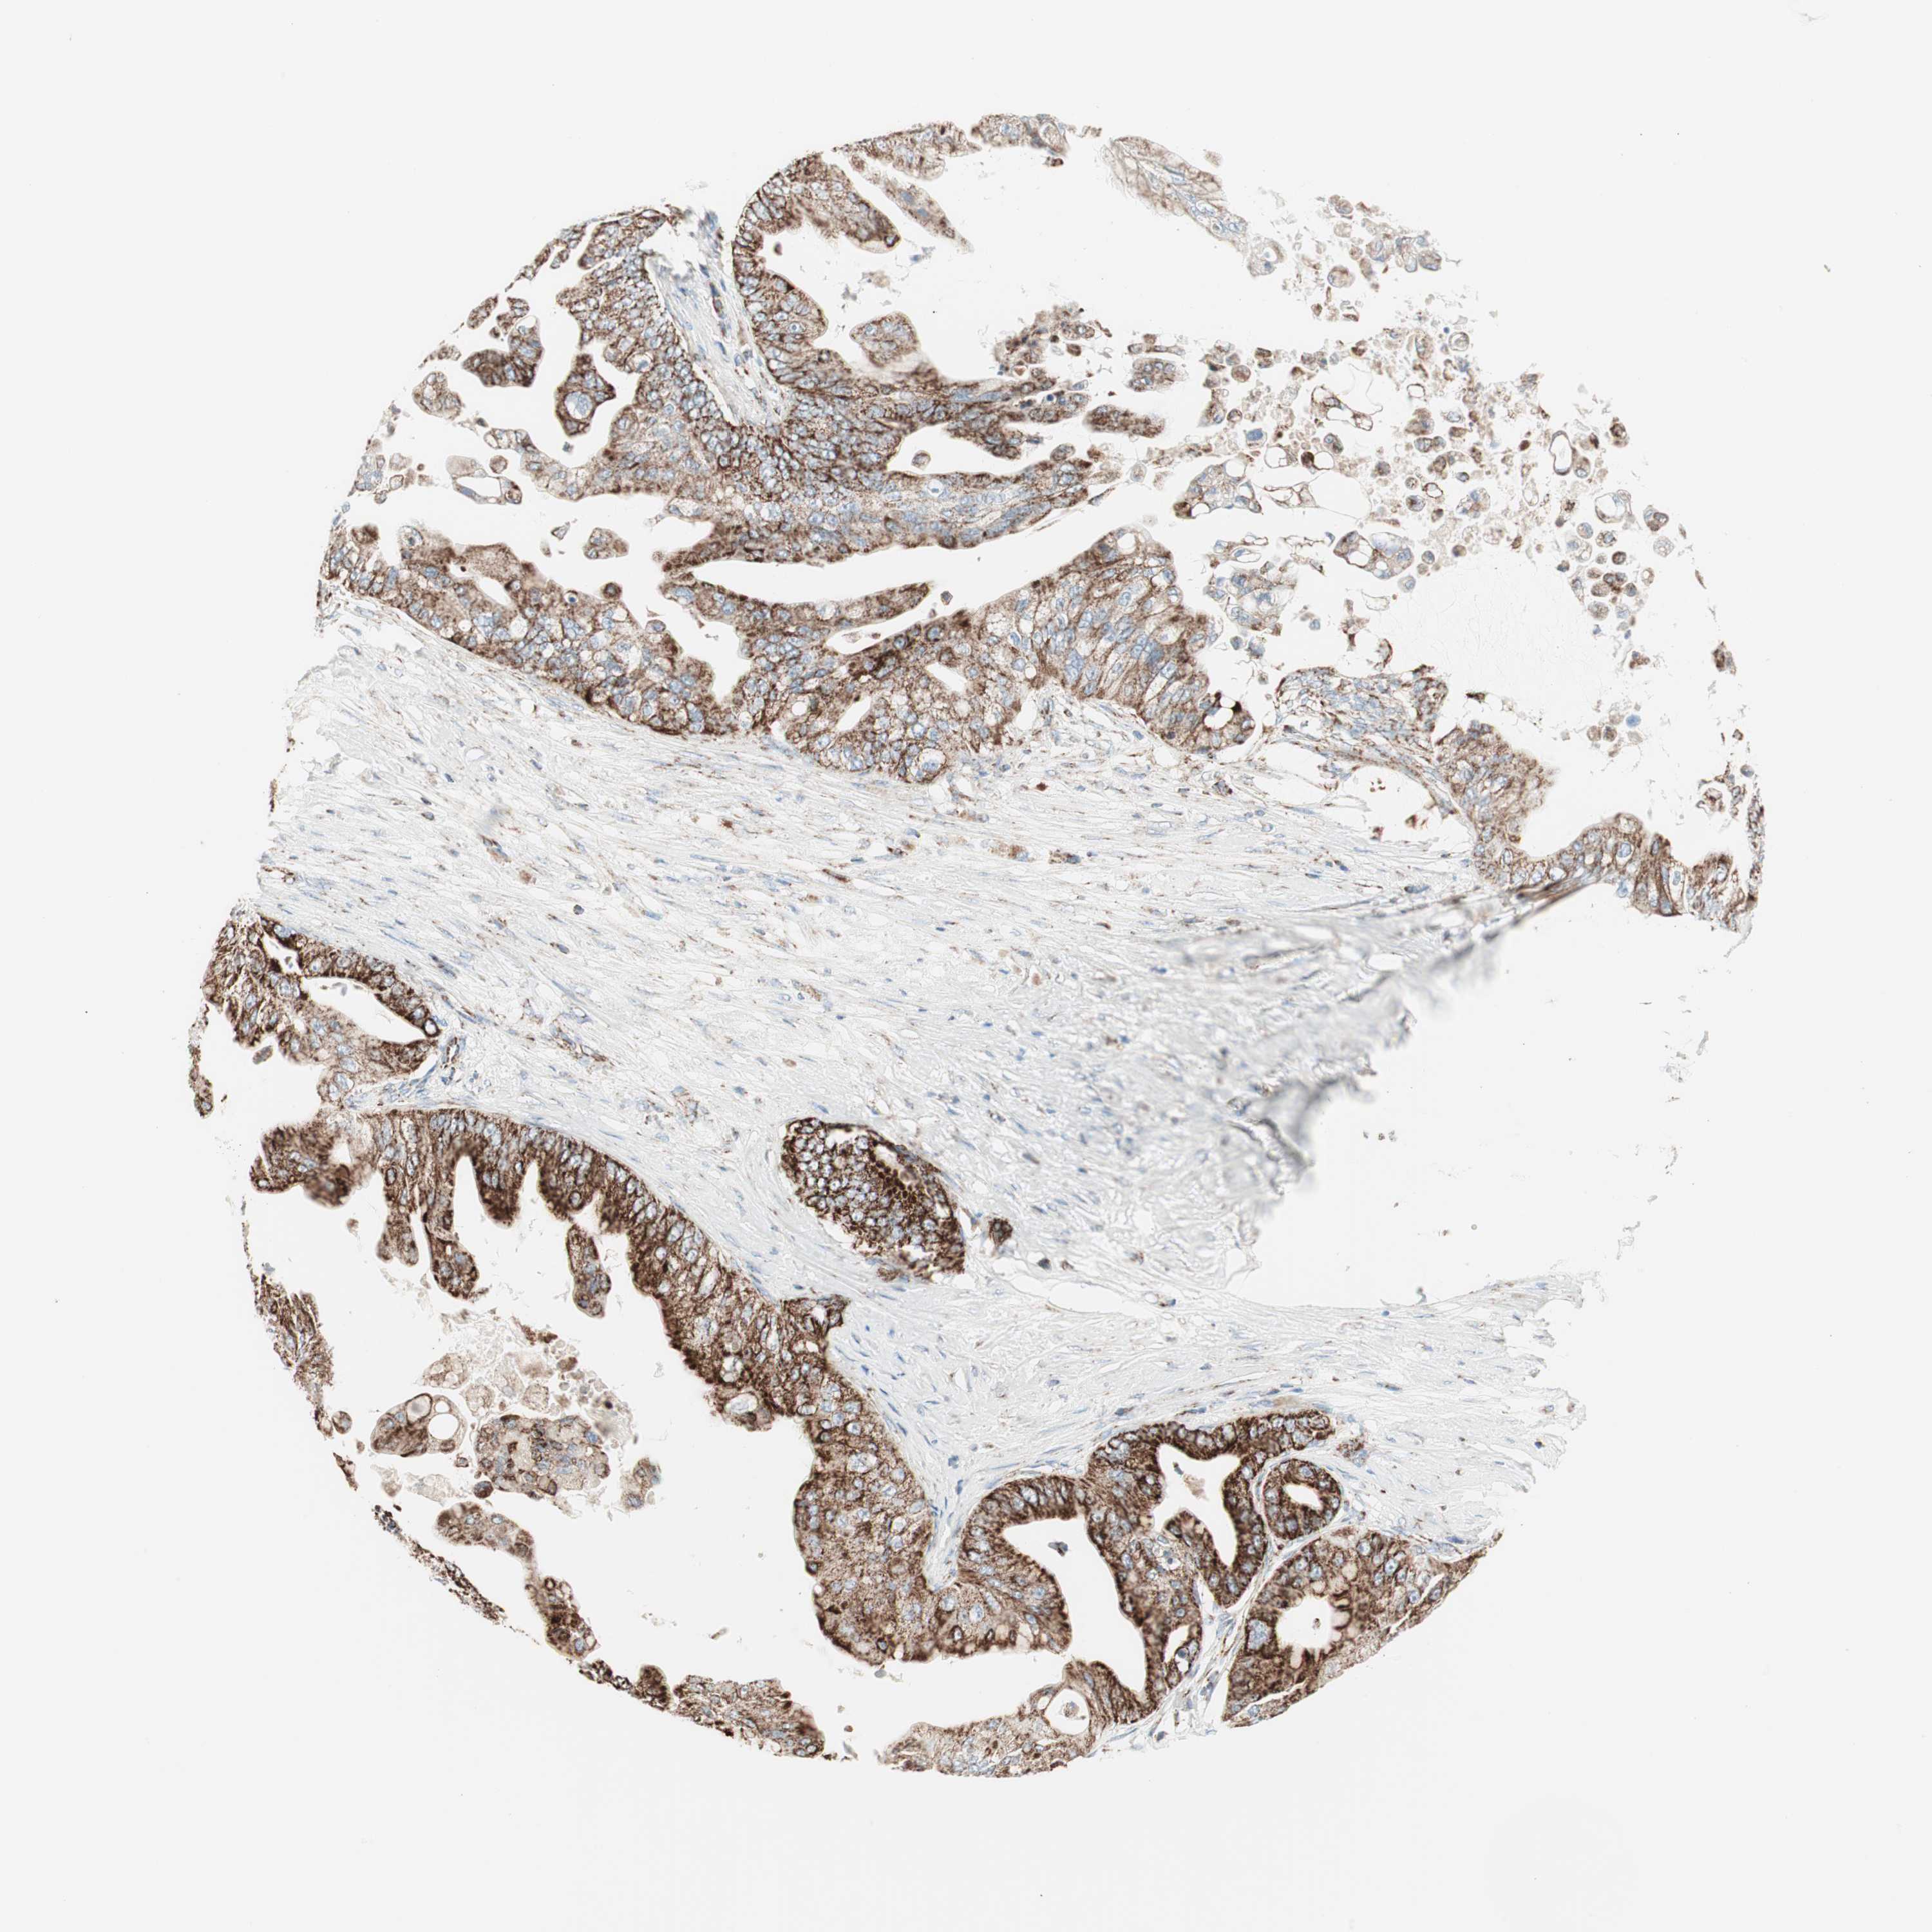

PANCREATIC CANCER - Protein expressioni

A mouse-over function shows sample information and annotation data. Click on an image to view it in a full screen mode. Samples can be filtered based on level of antibody staining by selecting one or several of the following categories: high, medium, low and not detected. The assay and annotation is described here.

Note that samples used for immunohistochemistry by the Human Protein Atlas do not correspond to samples in the TCGA dataset.

Antibody stainingi

Antibody staining in the annotated cell types in the current human tissue is reported as not detected, low, medium, or high, based on conventional immunohistochemistry profiling in selected tissues. This score is based on the combination of the staining intensity and fraction of stained cells.

Each image is clickable and will lead to virtual microscopy that enables deeper exploration of all samples and also displays staining intensity scores, fraction scores and subcellular localization as well as patient and tissue information for each sample.

Antibody HPA011562

Antibody CAB005585

Staining

High

Medium

Low

Not detected

Intensity

Strong

Moderate

Weak

Negative

Quantity

>75%

75%-25%

<25%

None

Location

Nuclear

Cytoplasmic/membranous

Cytoplasmic/membranous,nuclear

Adenocarcinoma, NOS

Adenocarcinoma, metastatic, NOS